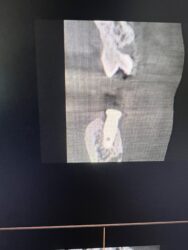

What are your thoughts on what this radiolucent area in the anterior mandible could be? Should I be concerened with placing an implant into it?

I’m not sure just from those slices but more reward and less risk in other locations. Around the mandibular midline you have your superior and/or inferior foramina relative to the genial tubercle/mental spine which can very in size greatly from pt. to pt. and often times very apical where no teeth have been before you can have more variability…

100% in agreement with @restoredsmiles While the anterior mandible is easy pickings for implants, it is very important to pay attention to things like this in the x rays.

It looks like if you drill into that spot you may get a bleeder that might be difficult to manage. I would also recommend opting for modifying your plan to stay away from that finding.